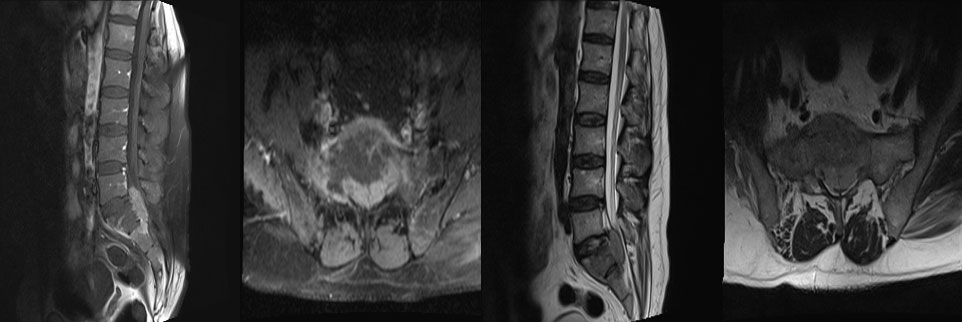

Ameliyat öncesi: MR’da birinci sakrum kemiğinin tamamını tutan ve spinal kanalı doldurup ciddi omurilik basısına neden olan tümör görülmekte.